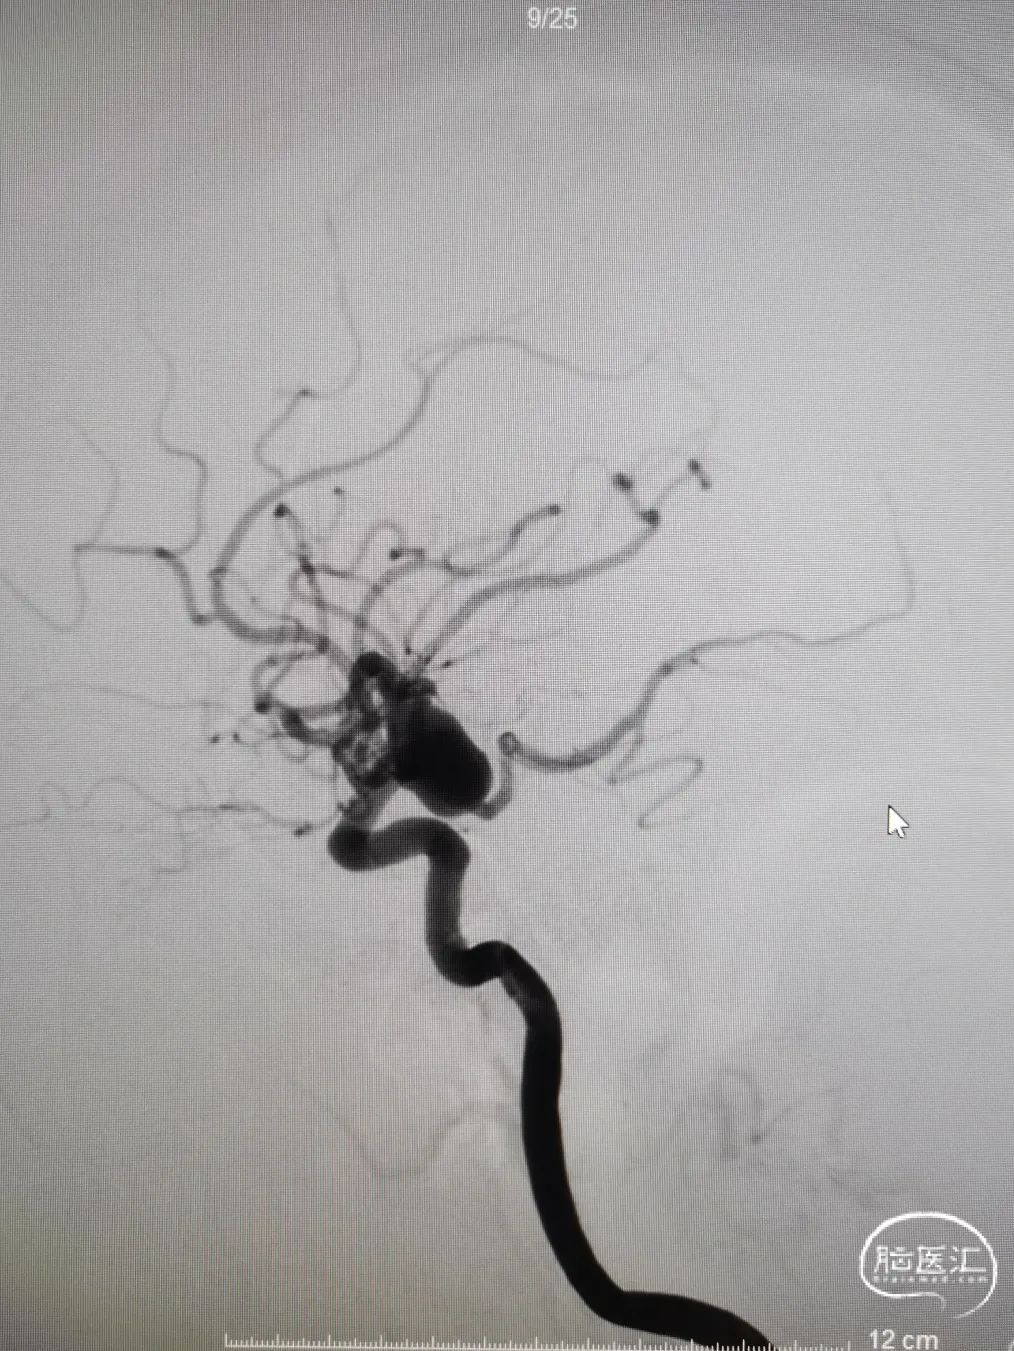

DSA造影

造影提示主动脉弓开口尚可,但颈动脉迂曲明显。

前交通囊状动脉瘤约4mm╳3mm,瘤颈约4mm。

右颈内动脉交通段以远瘤样扩张,载瘤动脉完全瘤化,局部可见多处小阜突起,无明显瘤颈,最大约16mm╳11mm。

右侧后交通动脉自瘤体远端发出。

右侧大脑中动脉直径约3mm,颈内动脉海绵窦段约4.5mm。

图4